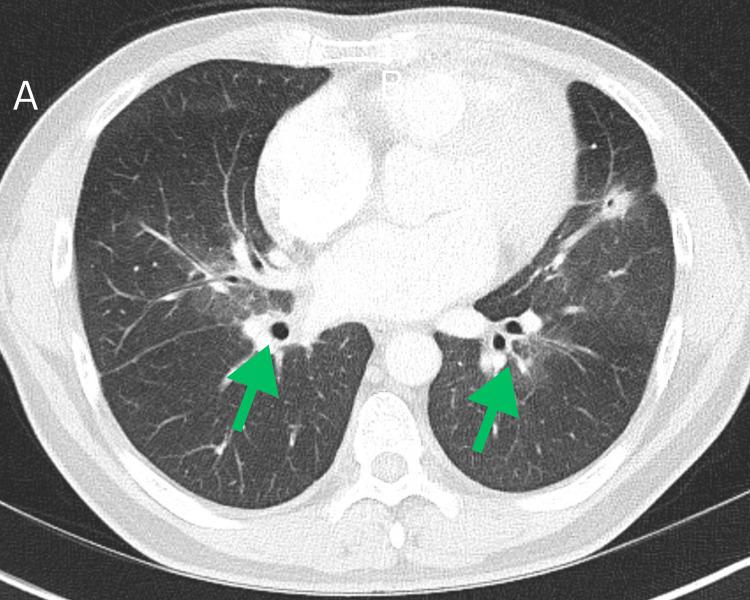

Lung cancer remains the leading cause of cancer-related deaths globally. While smoking-related lung cancers still account for most cases and cause approximately 100,000 deaths annually in the USA, smoking rates have been declining for decades. Lung cancer in never-smokers (LCINS), which tends to affect women and Asian populations, is now the fifth most common cause of cancer-related deaths worldwide. In 2023, over 20,000 lung cancer deaths in the USA were projected to occur in never-smokers, making LCINS the eighth leading cause of cancer-related mortality in the country. As the number of LCINS cases rises, it becomes increasingly important to explore the unique causes and characteristics of the disease, which calls for tailored diagnostic approaches and personalized treatment plans. Lung adenocarcinoma (LUAD) can present with atypical imaging features that often resemble benign conditions, including pneumonia, lung abscesses, post-infectious scarring, atelectasis, mediastinal masses, emphysema, and granulomatous disease. This variability in presentation can hinder accurate diagnosis and potentially delay timely treatment. While lung cancer is uncommon in younger individuals, with only 5.6% of new cases occurring in those under 54 years old, clinicians should maintain a high index of suspicion, as early detection is essential, and atypical cases can be easily missed. Here, we present a complex case involving an unusual radiologic manifestation of a lung mass, in which tuberculosis was initially considered the primary differential diagnosis.

肺癌仍然是全球癌症相关死亡的主要原因。虽然与吸烟相关的肺癌仍然占大多数病例,并且在美国每年导致约10万例死亡,但吸烟率几十年来一直在下降。从不吸烟者中的肺癌(LCINS),往往影响女性和亚洲人群,现在是全球癌症相关死亡的第五大常见原因。2023年,预计美国超过2万例肺癌死亡将发生在从不吸烟者中,使LCINS成为该国癌症相关死亡率的第八大原因。随着LCINS病例数量的增加,探索该疾病的独特病因和特征变得越来越重要,这需要量身定制的诊断方法和个性化的治疗方案。肺腺癌(LUAD)可能表现出非典型的影像学特征,这些特征通常类似于良性疾病,包括肺炎、肺脓肿、感染后瘢痕、肺不张、纵隔肿块、肺气肿和肉芽肿性疾病。这种表现的变异性可能会阻碍准确诊断并可能延迟及时治疗。虽然肺癌在年轻人中并不常见,只有5.6%的新病例发生在54岁以下的人群中,但临床医生应保持高度的怀疑指数,因为早期检测至关重要,非典型病例很容易被漏诊。在此,我们介绍一个复杂病例,涉及肺部肿块的不寻常放射学表现,其中最初将肺结核视为主要鉴别诊断。